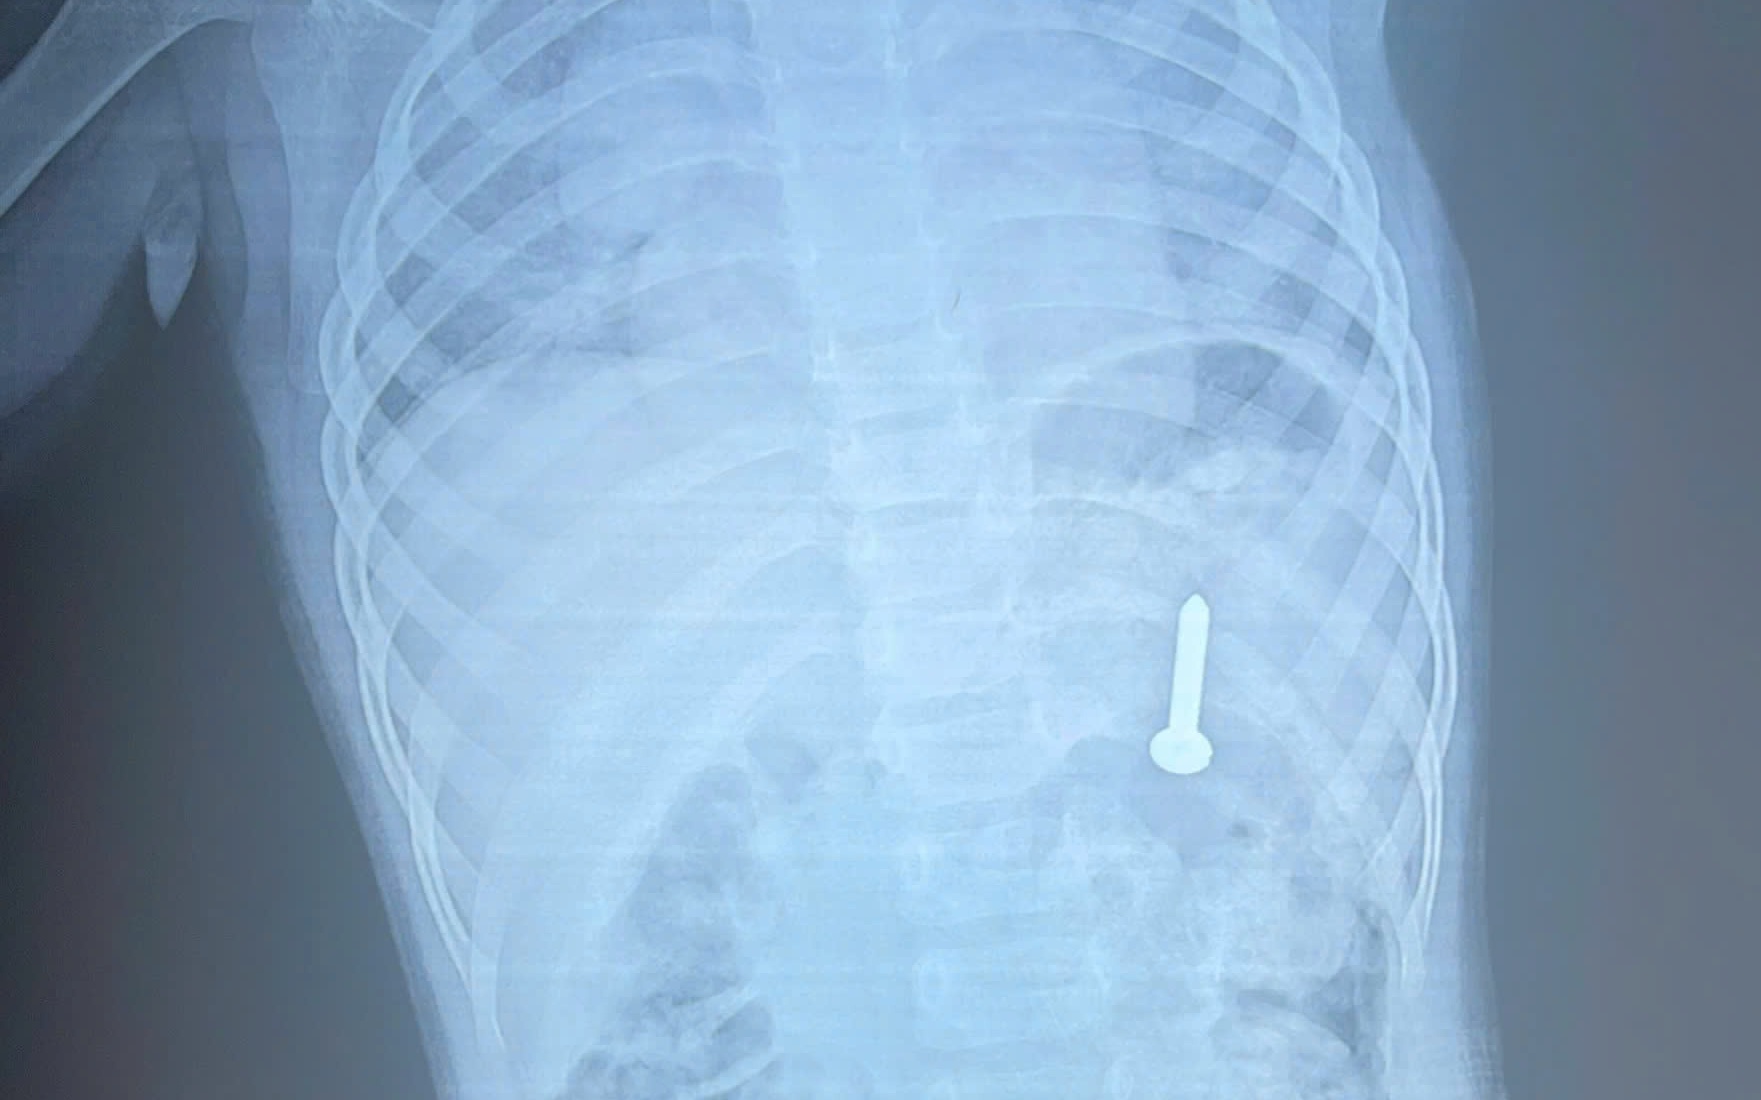

Hình ảnh chụp Xquang và đoạn kẽm nhung sau khi được bác sĩ phẫu thuật lấy ra ngoài

Tại bệnh viện, chỉ số SpO2 còn 90%, nhịp thở nhanh, co kéo cơ hô hấp, phế âm bên trái giảm nhẹ. Kết quả chụp X-quang và CT scan ngực ghi nhận có dị vật cản quang tại thùy dưới phổi trái.